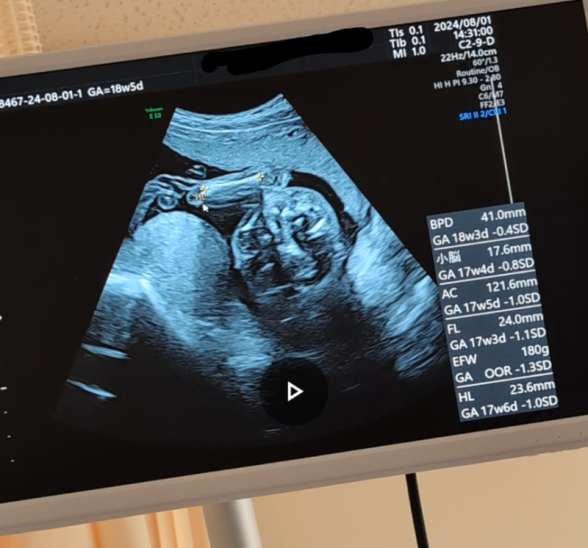

18W5D妊婦です。

本日 中期スクリーニングをやったのですが、(4Dではなかった)

先生は最後に一言、「異常なし」とはいわれたものの、

エコー中一切説明ないので不安です。

以外画像右下アルファベットや数字から読み取れることをお教えいただけませんでしょうか。

数値は、全て標準的な範囲内で問題なさそうですよ。